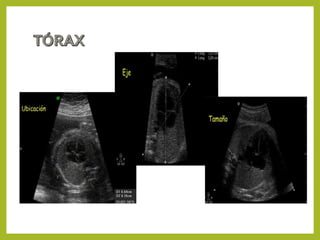

Tórax

• Situs cardiaco.

• Plano de las 4 cámaras.

• Se evaluará en planos sagital y axial.

• Identificar el situs, tamaño y ejes cardiacos.

• Corte de las 4 cámaras cardiaca.

• Evaluación de la salida de la arteria aorta (corte de las 5 cámaras).

• Evaluación de la salida de la arteria pulmonar (corte de los 3 vasos).

Corte de las 4 cámaras Corte de las 5 cámaras Corte de los tres vasos